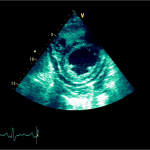

Ecocardiografia transtoracică

- Formaţiune hiperecogenă cu suprafaţa neregulată, care tapetează peretele liber al VD, grosime de 12 mm

- Dispusă de sub planul valvei tricuspide până in apropierea conului de ejecţie al valvei pulmonare

- SIV aplatizat

Ecografia transesofagiană:

Confirmă datele de la ecografia transtoracică